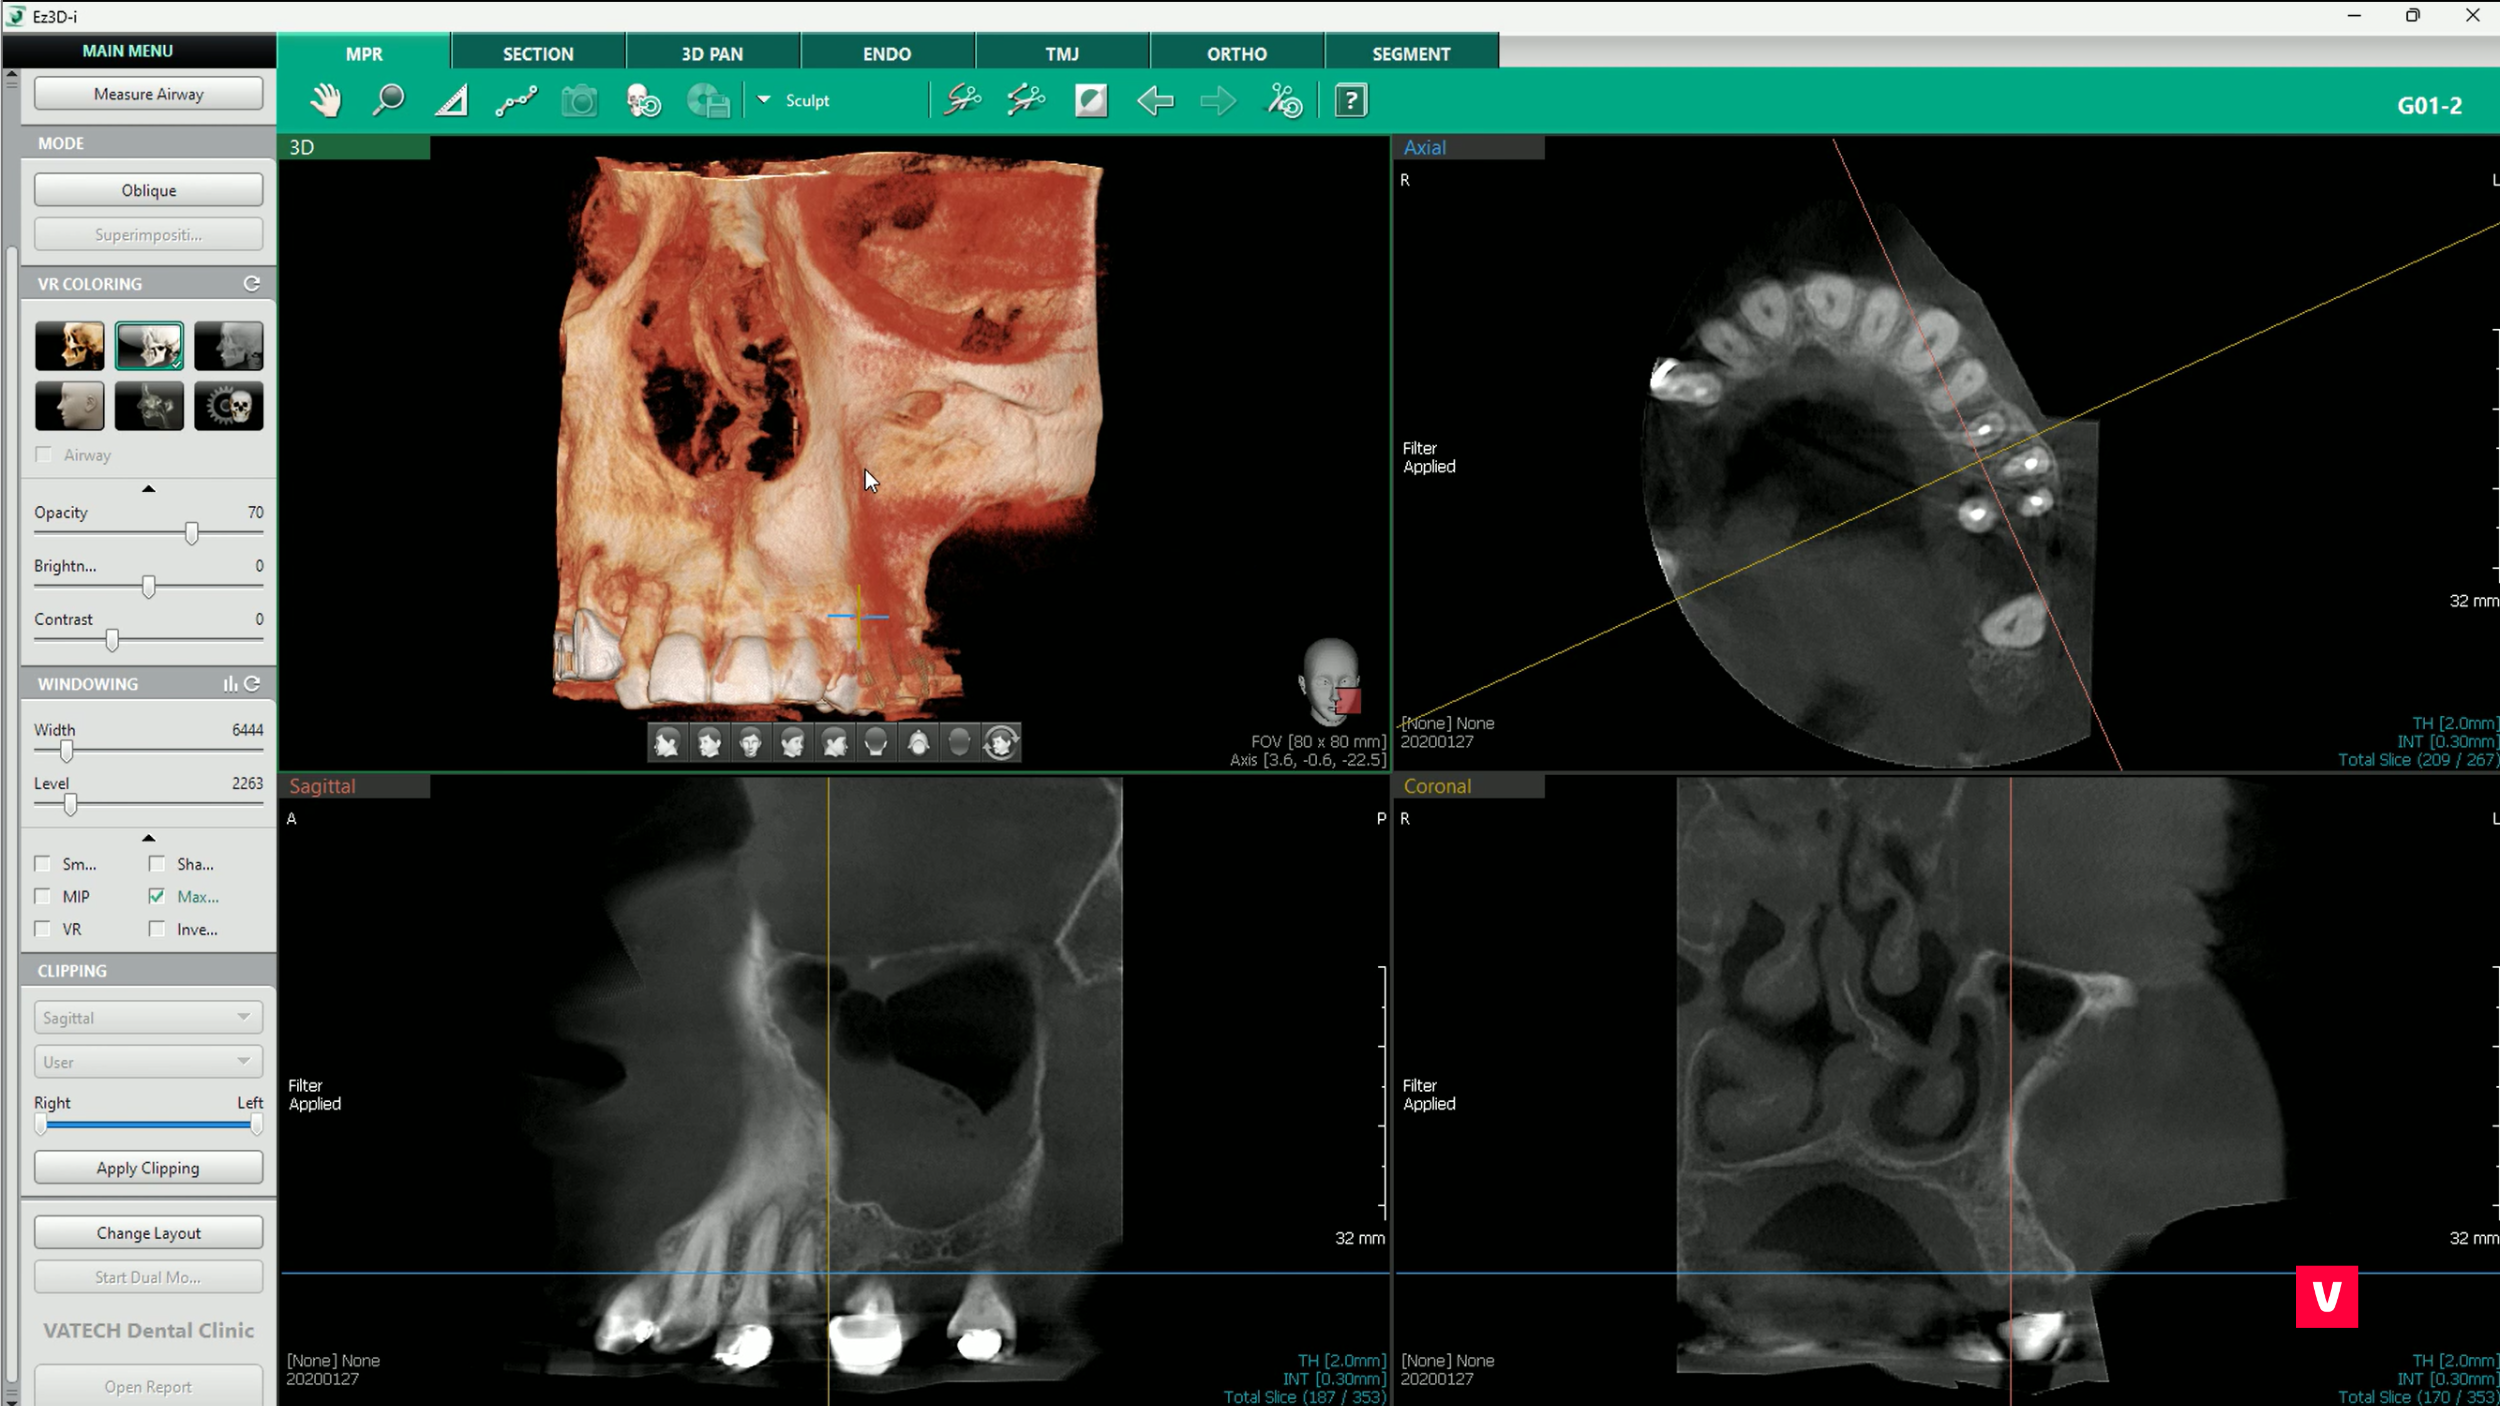

2. Dublu click

Funcția „dublu click” oferă un avantaj superior în fluxul de lucru, deoarece te ajută să găsești informațiile necesare prin zoom inteligent. Aceasta înseamnă că dacă găsim zona problematică din imaginea 3D și facem dublu click pe ea, funcția asistată de AI (inteligență artificială) va recunoaște automat același loc în toate planurile. Acest lucru permite o diagnosticare mult mai rapidă și fără erori.

Este una dintre multele comenzi rapide utile pe care le oferă software-ul Ez3D-i de la Vatech.